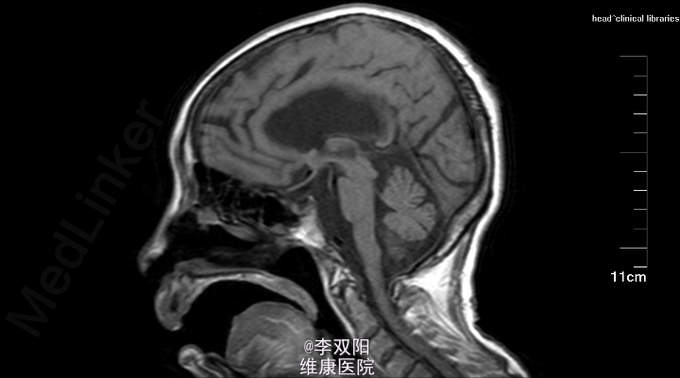

查体:体温36.2℃,脉搏58次/分,呼吸20次/分,血压150/90mmHg。轮椅推入病房,查体合作。皮肤巩膜无黄染,双肺呼吸音清,未闻及罗音,心率58次/分,律齐,无病理性杂音,腹部平软,肝脾肋下未触及。 神经系统专科查体:神志模糊,失语,双瞳孔同大同圆,直径3.0mm,对光反射灵敏,眼球各方向可活动,无眼震及复视,鼻唇沟对称,咽反射(+),伸舌不合作,四肢肌力2级,肌张力增高,肱二头肌、肱三头肌肌腱及膝反射、跟腱反射均对称,感觉及共济运动检查不合作,Hoffmann征L(-),R(-),病理征:Babinski征L(+),R(+),颈无抵抗,Kernig征(-)。 辅助检查:头颅CT扫描示:双侧基底节区及丘脑区斑片状低密度影,双侧脑室周围及双侧半卵圆中心见片状密度减低区,边缘模糊不清。双侧脑室扩张,脑沟裂增宽,中线结构居中。 头MRI+DWI:双侧基底节区及丘脑区斑片状低密度影,双侧脑室周围及双侧半卵圆中心见片状密度减低区,边缘模糊不清。双侧脑室扩张,脑沟裂增宽,中线结构居中。

因无肢体震颤及运动减少,暂可除外帕金森病,现四肢肌张力明显增高,且影像学提示颅内广泛萎缩,不除外进行性核上性麻痹,患者现病史不详,不能明确变性病病种,给予对症治疗,注意预防褥疮,预防离子紊乱,注意避免呛咳而引起坠积性肺炎。